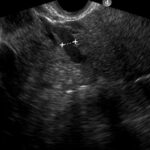

Fig. 2: a) Examen ecográfico por vía transvaginal, que muestra vena ovárica izquierda ectásica de 7.5 mm. b) Examen ecográfico por vía transvaginal, demostrando vena ovárica derecha normal, de 2.5 mm.

Hallazgos imagenológicos. En el eco Doppler ginecológico por vía transvaginal se observa varicocele pelviano (Fig. 1). La vena ovárica derecha mide 3.8 mm, y la izquierda, ectásica, 7.4 mm (Fig. 2). En el eco Doppler abdominal se visualiza la vena renal izquierda, de 3.1 mm en topografía del compás aorto-mesentérico y 8.1 mm en el segmento proximal al riñón izquierdo, con una velocidad 50cm/s en el compas y 30cm/s en el segmento proximal al riñón. El estudio corresponde en primera instancia a un síndrome de Nutcracker (Fig. 3).